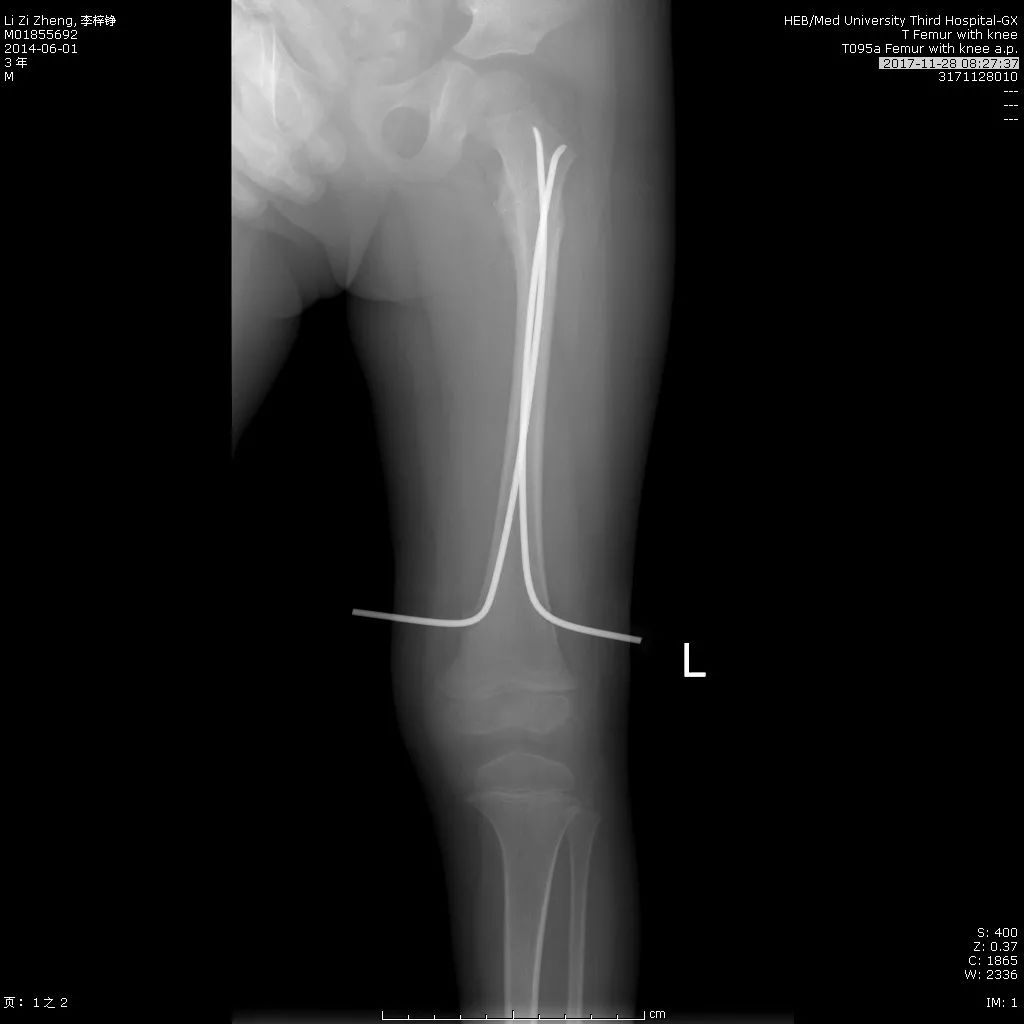

此处应用钢板有两种情况一是不会使用髓内固定,设备条件达不到;再就是理念落后见的病例少,交流少。此处外侧全部是长应力,钢板为张力钢板,内收肌力量强大,目前的钢板不能承受反复的弯曲应力,金属疲劳断裂失败率高,以下病例切开,钢丝捆绑进一步骨膜剥离,破坏了原始血肿,干扰骨愈合,都是失败原因

补救办法:剥削植骨髓内钉固定或动力髁钢板固定。

补救比较好

补救:取下一枚钉子骨折愈合了,关键是取钉子后减少了应力集中,延长了钢板的寿命,骨折愈合了。如果骨不愈合钢板迟早断裂(钢板当初放在内侧会好,蝶形骨块不会坏死,腓骨固定后外侧稳定,内外柱均衡愈合机会增加,当然最好还是髓内钉)。

取下3枚钉子骨折愈合了,与上一例同一位医生所做。张力带钢板,去除3螺钉后,钢板的应力分散,弹性增加,骨折端承受有效的应力刺激,最后骨折愈合。去除螺钉的时候如果加骨皮质剥离重新激发骨愈合会更好。(最好选髓内钉)